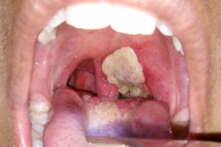

Dịch bạch hầu lan rộng tại miền tây Quảng Trị